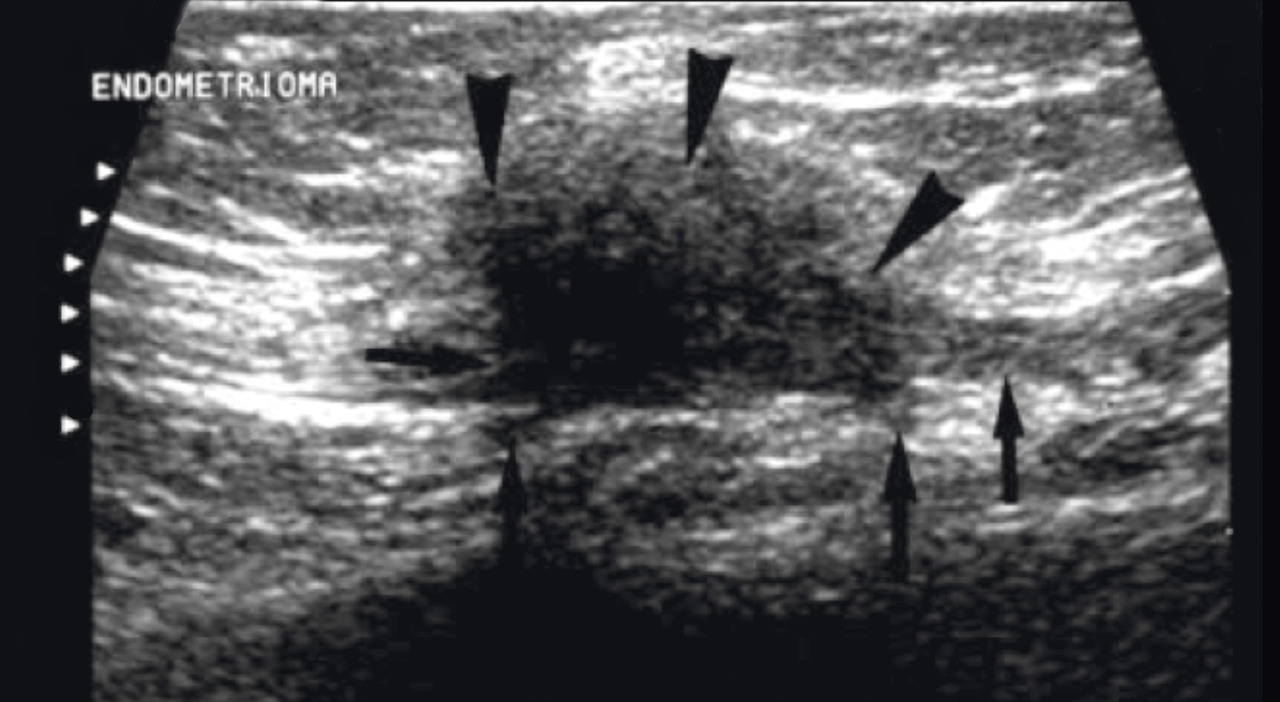

L’échographie pariétale est privi- légiée ; elle permet de localiser, me- surer et suspecter le nodule endo- métriosique dans la cicatrice de césarienne mais aussi de confirmer dans certaines situations les diagnostics différentiels. Il est conseillé, au mieux, de faire une échographie en crise pendant les règles et une en dehors des règles pour mettre en évidence le caractère fluctuant du nodule.27,29 Cependant, une échographie en dehors des règles retrouve déjà une image assez typique (fig. 1).